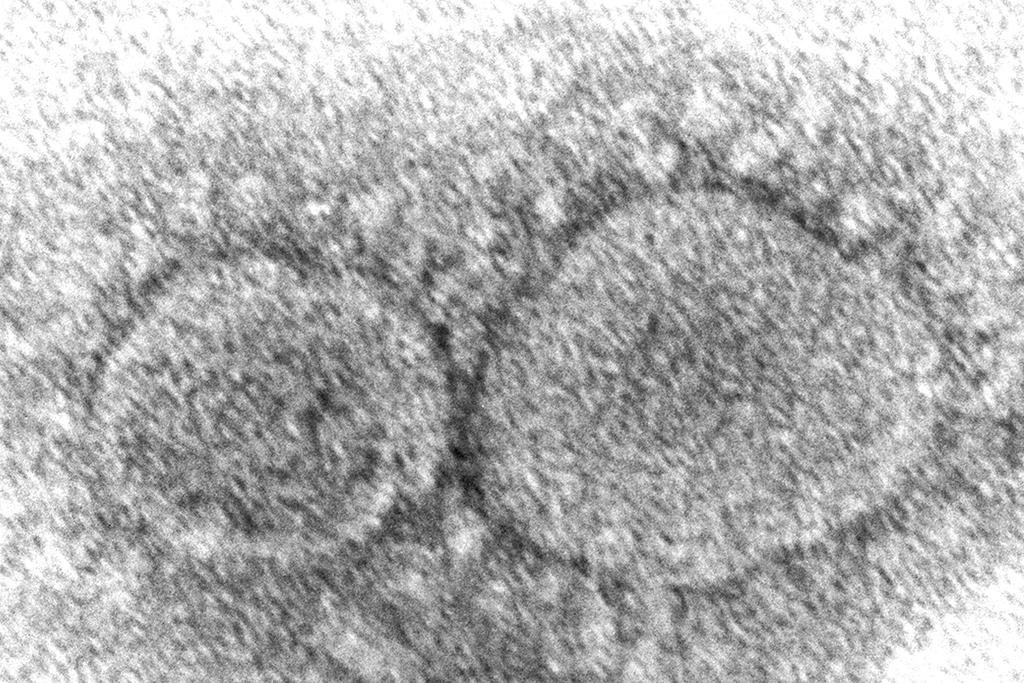

On pourrait détecter le coronavirus sur les planchers

MONTRÉAL — Il semble possible de détecter la présence du coronavirus sur les planchers, ce qui pourrait donner aux responsables un préavis de quelques jours avant une éclosion, démontrent des travaux en partie réalisés à Montréal.